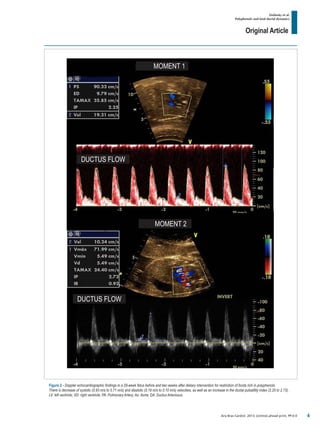

Figure 2 - Doppler echocardiographic findings in a 29-week fetus before and two weeks after dietary intervention for restriction of foods rich in polyphenols.

There is decrease of systolic (0.93 m/s to 0.71 m/s) and diastolic (0.19 m/s to 0.10 m/s) velocities, as well as an increase in the ductal pulsatility index (2.25 to 2.73).

LV: left ventricle; VD: right ventricle; PA: Pulmonary Artery; Ao: Aorta; DA: Ductus Arteriosus.